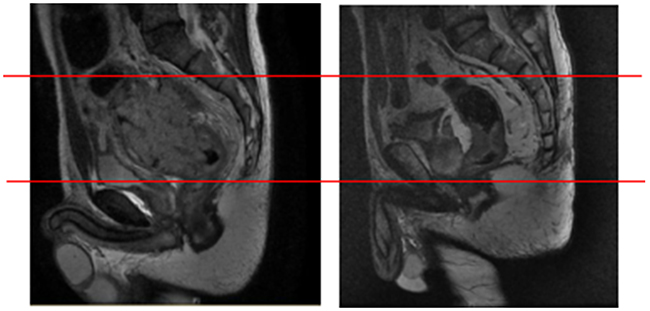

Thirdly, the location and size of the primary tumor are important determinants of the site of pelvic recurrence. For instance, as shown in Figure 1, two patients whose records showed that the tumors were almost equidistant from the anal verge showed totally different failure patterns. Therefore, some modifications are essential when applying our recommendations in clinical practice. In cases of distal rectal tumors, the upper pelvis could be omitted for cases in which the upper border of the gross tumor was more than 2 cm away from the base of the sacroiliac joint. This hypothesis will be validated in the further prospective studies.

Figure 1: Representative images of two patients with pelvic recurrence. Representative images of two patients who had tumors that were almost equidistant from the anal verge. Both patients showed totally different failure patterns, with recurrence occurring at different pelvic sites.